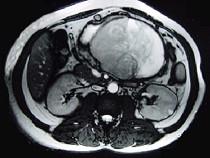

问题 男,36岁,腹胀、消化不良、消瘦、中上腹痛,影像检查如下图,最可能的诊断是()

选项 A.胃间质肉瘤并肝转移 B.胃间质瘤并原发性肝癌 C.内胚窦瘤肝转移 D.胃淋巴瘤伴原发性肝癌 E.胃间质瘤并肝血管瘤

答案 A